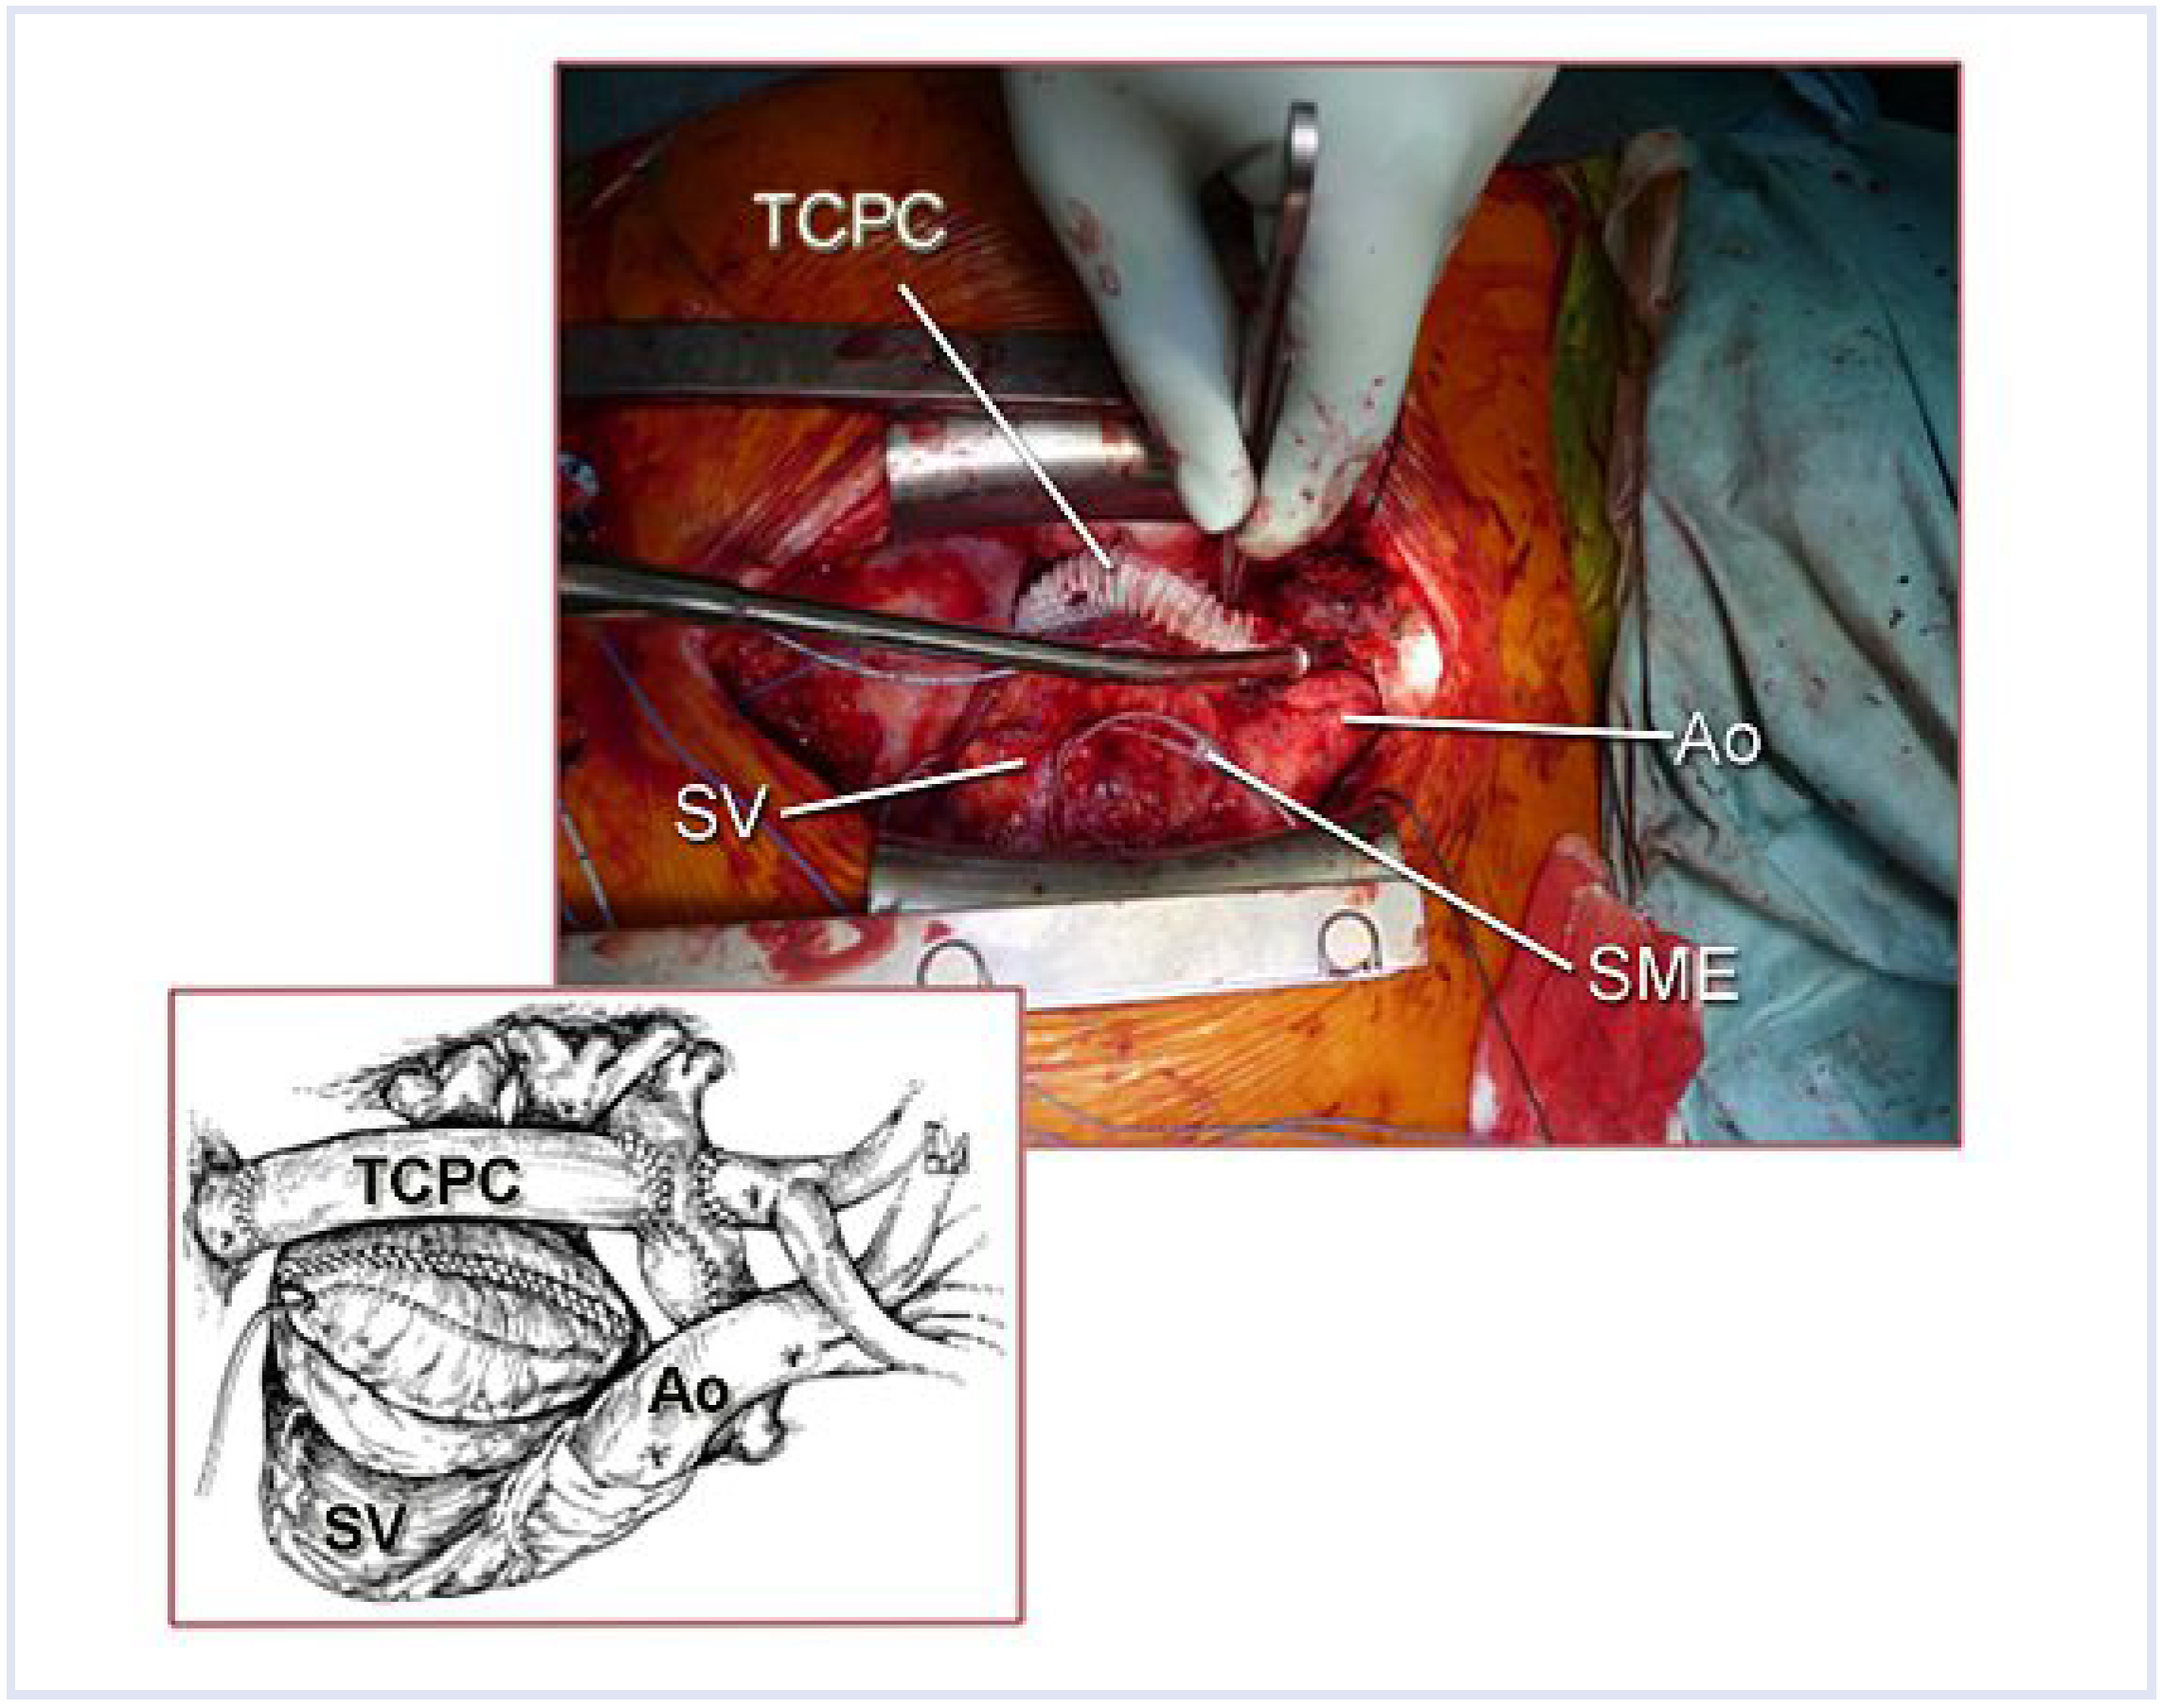

Abbildung 4.

Intraoperativer Situs nach «Fontan-Konversion»: Status nach Implantation eines 19-mm-PTFE-ringverstärkten extrakardialen Conduits (TCPC), Vorhofreduktionsplastie und Implantation von linksatrialen und systemventrikulären epikardialen Vorhofelektroden. TCPC = totale cavo-pulmonale Konnektion; Ao = Aorta; SME = epikardiale Schrittmacherelektroden; SV = Systemventrikel.

Abbildung 4.

Intraoperativer Situs nach «Fontan-Konversion»: Status nach Implantation eines 19-mm-PTFE-ringverstärkten extrakardialen Conduits (TCPC), Vorhofreduktionsplastie und Implantation von linksatrialen und systemventrikulären epikardialen Vorhofelektroden. TCPC = totale cavo-pulmonale Konnektion; Ao = Aorta; SME = epikardiale Schrittmacherelektroden; SV = Systemventrikel.

Nach Resternotomie und ausgedehnter Adhäsiolyse, insbesondere des massiv dilatierten rechten Vorhofes, wurde die Patientin mittels arteriell-aortaler und venöser-bicavaler Kannulation an die Herz-Lungen-Maschine angeschlossen. Das rechte Atrium wurde eröffnet und die Anastomose zur Pulmonalarterie identifiziert. Nach ausgedehnter Resektion der antero-lateralen Vorhofswand bis auf ca. ¼ der ursprünglichen Grösse wurde das intraatriale Septum reseziert. Dies ermöglichte eine ungestörte Drainage des Sinus coronarius in den linken Vorhof. Nach Durchführung einer rechtsatrialen Kryoablation wurde die VCI am Eintritt zum Atrium abgesetzt und der Vorhof verschlossen. Für die Herstellung der VCI-Pulmonalis-Kontinuität wurde eine 19-mm-ringverstärkte PTFE-Gefässprothese gewählt, welche End-zu-End mit der VCI und End-zu-Seit am inferioren Aspekt der zentralen Pulmonalarterie am Ort der vorherigen atriopulmonalen Verbindung anastomosiert wurde. Aufgrund der angestrebten Anastomose mit dem Truncus pulmonalis und der Umgehung des rechten Atriums liess sich eine leichte Bogenform des Goretex-Conduits nicht vermeiden. Die Vena cava superior wurde End-zu-Seit mit der rechten Pulmonalarterie anastomosiert. Abschliessend wurde ein epikardiales Zwei-Kammer-Schrittmachersystem mit Antitachykardie-Funktion implantiert (Abb. 4). Unmittelbar postoperativ wurde die Patientin mit Cordarone aufgesättigt und mit DDD-Modus mit einer Frequenz von 120/min stimuliert. Es wurde eine frühzeitige Extubation angestrebt.